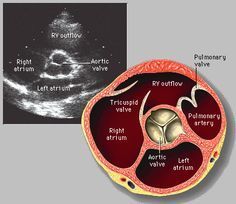

W kręgu zainteresowań pozostają: kardiologia ogólna, choroby wewnętrzne, diagnostyka obrazowa ( USG serca ), intensywna terapia kardiologiczna, mechaniczne wspomaganie krążenia.

* USG - echo serca

Najbardziej specyficznym badaniem będzie USG serca, najlepiej u kardiologia zajmującego się wadami wrodzonymi - w Polsce działają również Poradnie GUCH ( dorośli z wadami wrodzonymi ). Wskazane jest zabranie na taką konsultację pełnej dokumentacji medycznej, wpisu ze szpitala po korekcji wady. Pozdrawiam.